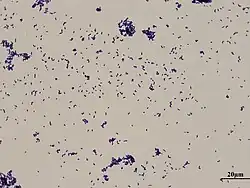

Corynebacterium xerosis

Corynebacterium xerosis (K.B. Lehmann & R. Neumann, 1896) K.B. Lehmann & R. Neumann, 1899